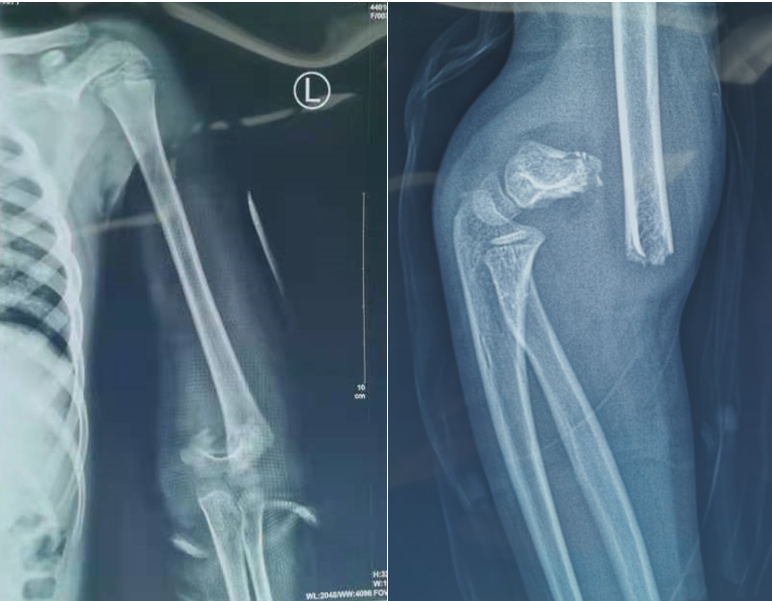

屈曲型肱骨髁上骨折

屈曲型肱骨髁上骨折,骨折伸直型和屈曲型图

骨折伸直型和屈曲型图

肱骨髁上骨折屈曲型图

肱骨髁上骨折图片

肱骨髁上骨折分型图片

肱骨髁上骨折分型

伸直型肱骨髁上骨折

肱骨髁上骨折